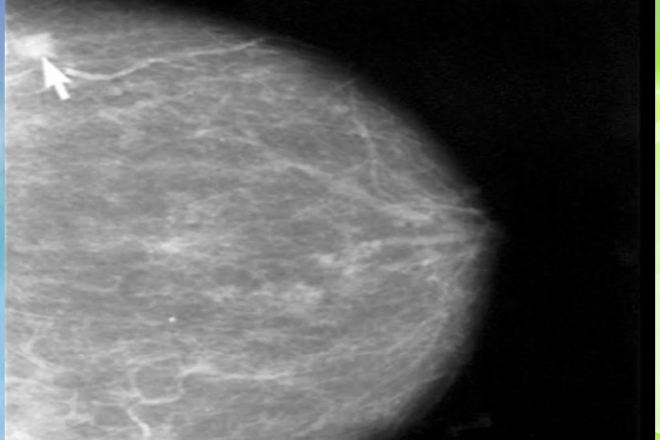

El ultrasonido es una herramienta de gran utilidad en la valoración del endometrio considerándose  un método de abordaje inicial, de fácil acceso y bajo costo; existen 3 modalidades de ultrasonido para su evaluación (pélvico, transvaginal e histerosonografía). El ultrasonido pélvico tiene una sensibilidad para detectar enfermedad endometrial del 70% y una especificidad del 60%. El ultrasonido transvaginal tiene una sensibilidad de un 95% y una especificidad del 61%, con una agudeza diagnóstica para invasión miometrial del 77%. La histerosonografía tiene una sensibilidad del 97% y una especificidad de un 82%, con un valor predictivo positivo del 82% y valor predictivo negativo de un 94%5,6.

Estudios clínicos aleatorizados han demostrado que, si bien el uso de tamoxifeno aumenta el riesgo de cáncer de endometrio, el beneficio neto que ofrece al aumentar la supervivencia libre de progresión del cáncer de mama es mayor. La valoración del grosor endometrial se realiza por cortes longitudinales y transversales desde el fondo uterino, midiendo la distancia existente entre su lámina basal anterior y posterior, abarcando las 2 caras endometriales y excluyendo la capa interna hipoecoica circundante del miometrio interno, con lo que se obtiene el grosor bioendometrial teniendo como medida normal de 3 a 5 mm. En los casos en los que las superficies endometriales están separadas por líquido, el grosor endometrial unilateral se mide en el lugar de máximo grosor. Para esta medida se requiere de una metodología para ser considerada válida.